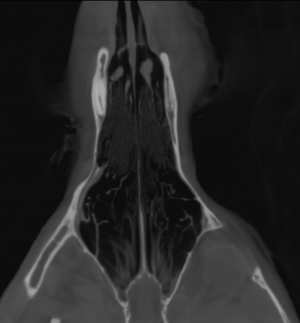

CT – Normal nasal cavities in a 6 year old MN German Shepherd with ulcerated swelling in nares

This 6 year old German Shepherd mix has a swollen area on the inside of the right nares with some loss of pigment and mild ulceration. ALKP mildy decreased, Eos mildly increased.

The tooth element 208 is absent and small gas bubbles are noted in the respective empty alveolar crests. The overlying soft tissues at this level present mild irregular margins. The nasal cavity presents the expected aerated spaces between thin & even conchae and turbinates with smooth mucosal lining. The nasal bones are within normal limits. The nasal passages are patent. There is no evidence of a mass lesion or rhinitis. The frontal sinuses are aerated and within normal limits.

No evidence of a nasal mass lesion or rhinitis